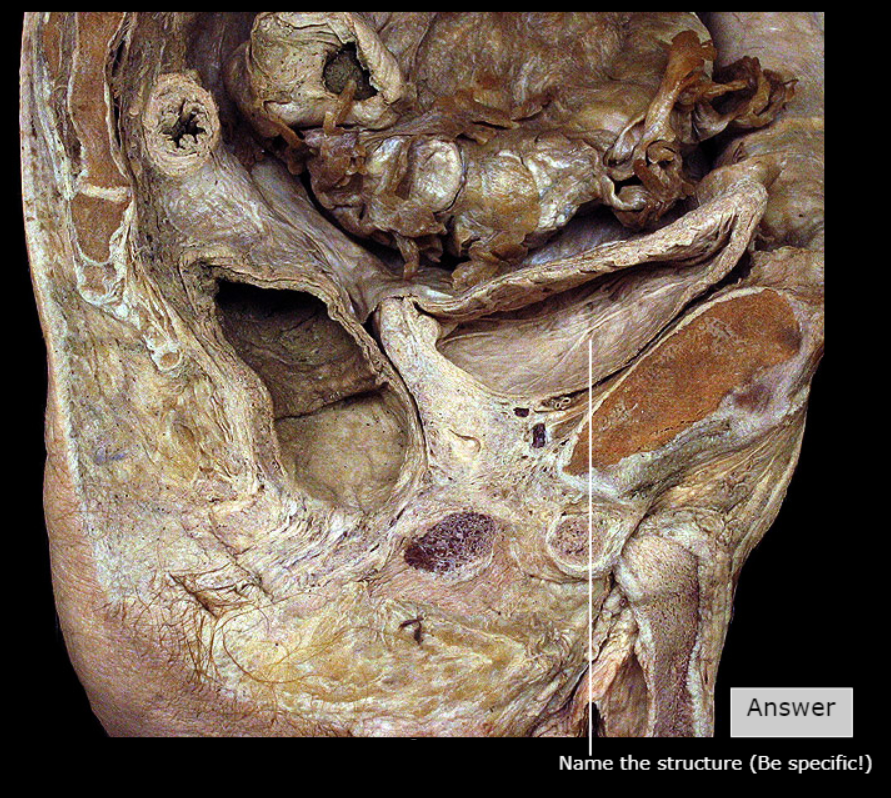

Crus of Clitoris